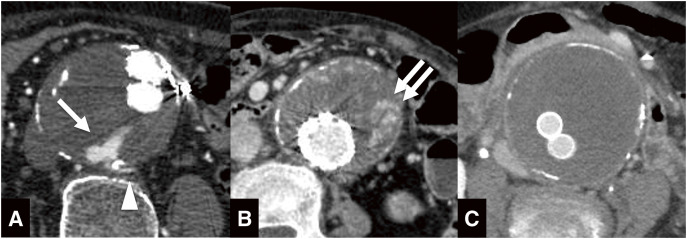

Objectives: The purpose of this study is to evaluate the feasibility and clinical outcomes of vasa vasorum embolization for preventing continuous aneurysmal expansion after endovascular aneurysm repair (EVAR). Methods: We retrospectively reviewed the medical records of patients who underwent vasa vasorum embolization between August 2018 and May 2022. Vasa vasorum embolization was attempted in cases of continuous aneurysmal expansion after EVAR, where the vasa vasorum was identified through catheter angiography. The vasa vasorum was accessed and embolized with a microcatheter. The outcomes of vasa vasorum embolization were evaluated based on technical success, defined as the successful completion of the embolization procedure, and clinical success, defined as the prevention of continuous aneurysmal expansion after the embolization. Results: Seven cases of endoleak with developed vasa vasorum were confirmed by catheter angiography. The mean age was 83.7 years, and the mean aneurysmal diameter was 60.6 mm. Technical success was achieved in 6 cases, while clinical success was not achieved in any of the cases. The mean observation period was 16.5 months, and the mean increase in aneurysmal diameter was 9.7 mm. Conclusions: Although the vasa vasorum embolization is a technically feasible procedure, it is not effective in preventing continuous aneurysmal expansion.

Abstract Image